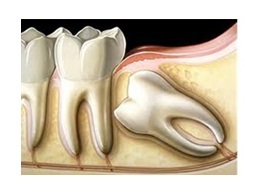

yang lalu sebelum aku memasang braces pada gigiku, aku telah dirontgen

terlebih dahulu. Aku tidak menyimpan hasil foto rontgenan ku karena

hasilnya diambil oleh dokter ortho yang menangani perawatan braces ku, jadi kurang lebih waktu itu hasilnya seperti ini pada bagian gigi gerahamnya:

Gigi

bungsu ini posisinya miring dan jika ia ingin numbuh nantinya, gigi

geraham yang di sebelahnya akan tertabrak dan rasanya sakit sekali.

Untuk itu, dokter ortho ku mengharuskan aku menjalani operasi

odontektomi, agar gigi bungsu yang miring ini segera dicabut, dan tidak

mengganggu gigiku selama perawatan braces nantinya.